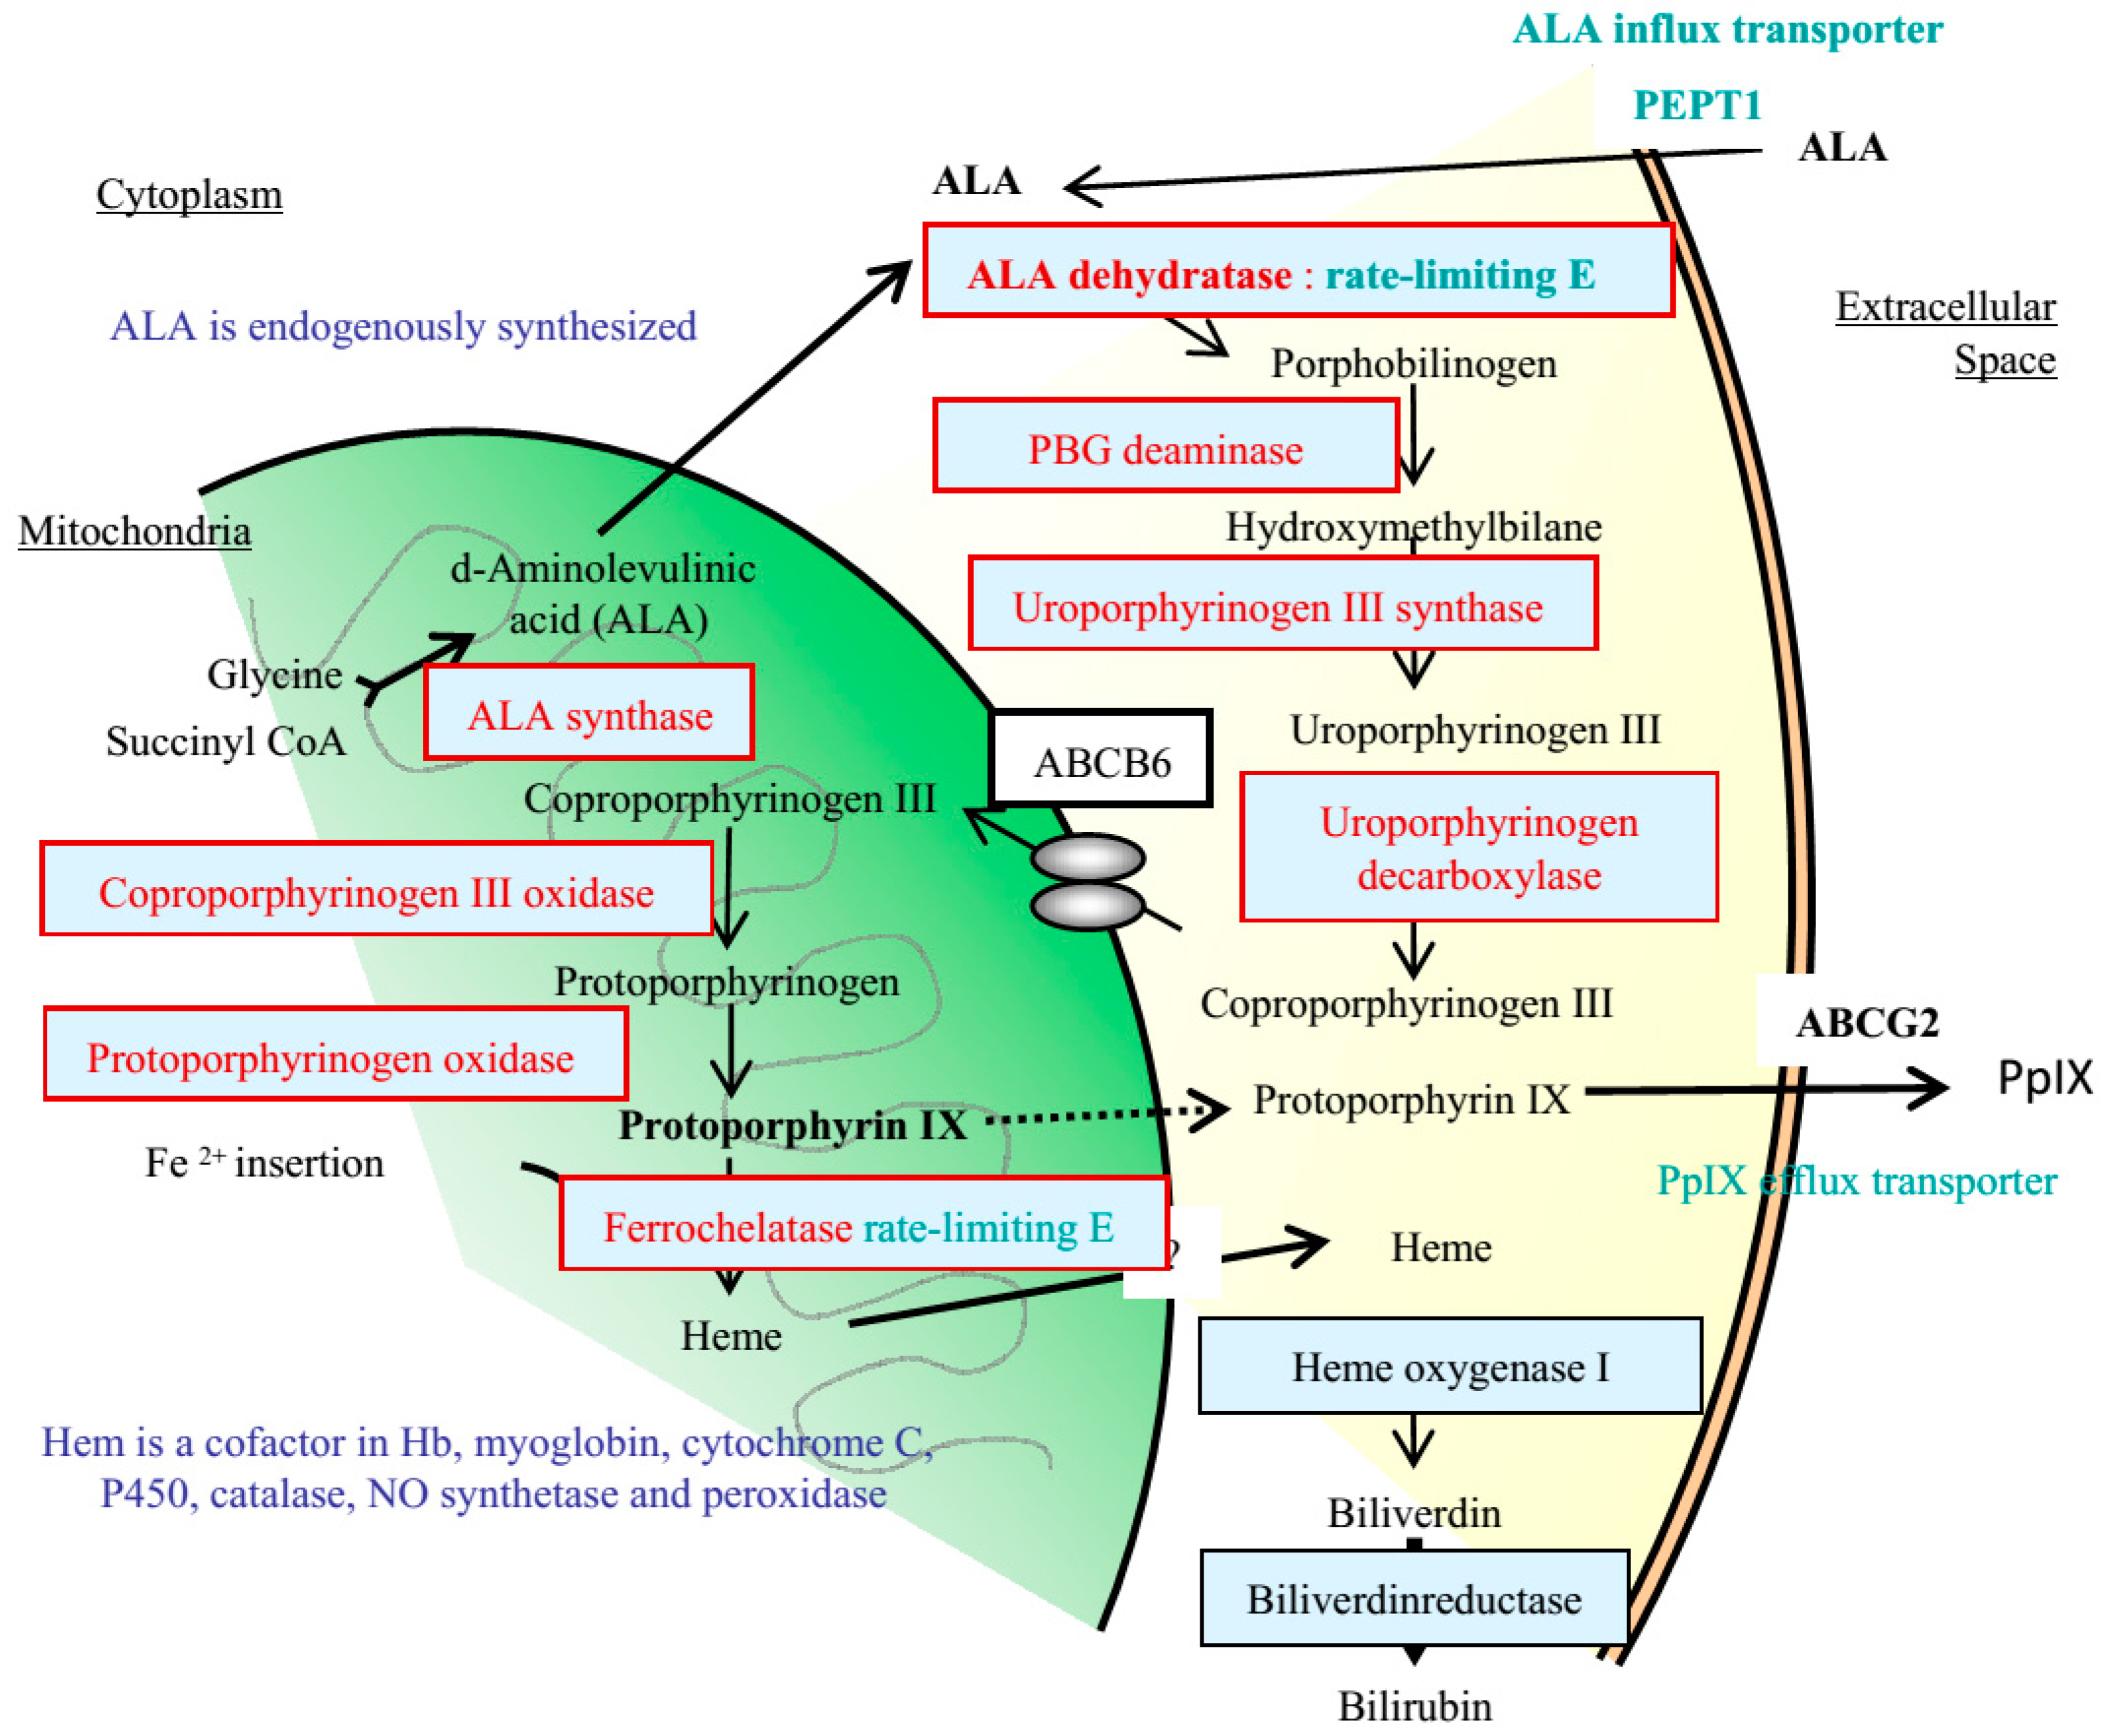

2. Rationale of Photodynamic Diagnosis (PDD) to Detect Peritoneal Metastasis Using 5-Amino-levulinic Acid

3. Molecular Mechanisms of Selective Accumulation of 5-ALA and PpIX in Cancer Cells and Cancer Tissues